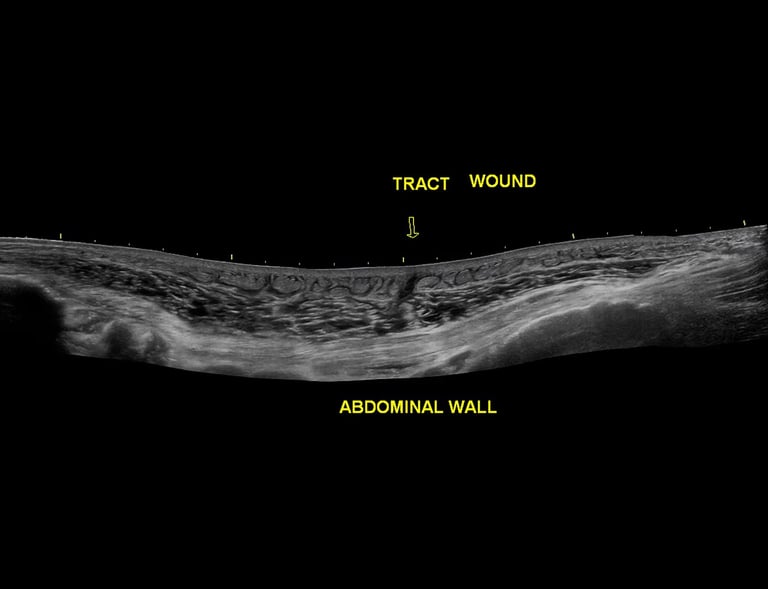

General Scans

Comprehensive radiological ultrasounds tailored to your health needs.